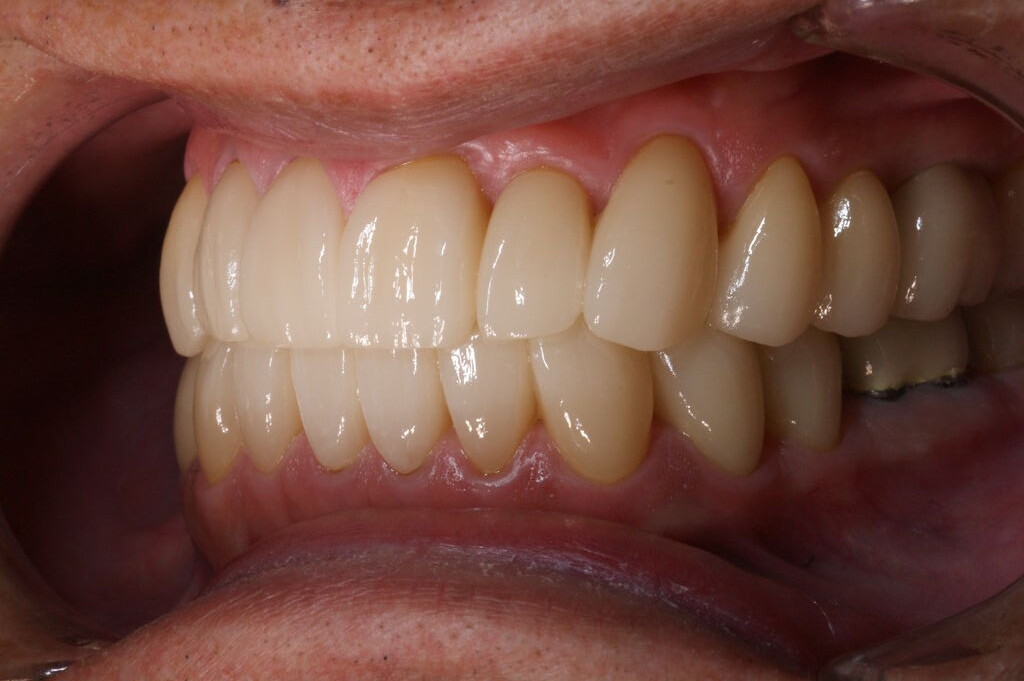

矯正治療終了後、模型を咬合器に付着し診断用ワクシングをしたところ、本来歯牙は咬合調整か小規模の修復処置で済めば極力そのまま使うのが理想ではあるが、長年の不正咬合とブラキシズムによる高度の磨耗のため、修復処置なしでは安定した咬合に基づく長期的な口腔内の健康は得られないとの判断に至る。

一口腔単位の長期的な健康維持のため、安定した咬合の確立と審美性の獲得を意図し全顎的修復処置を行う。(大)